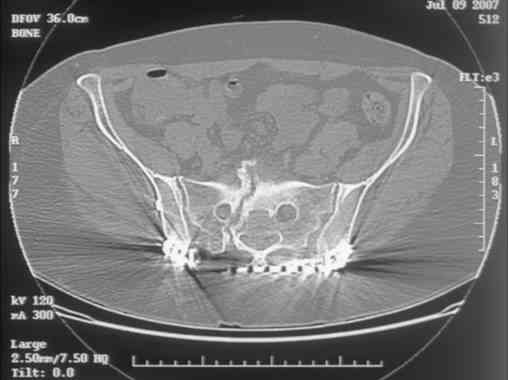

[Ortho] Sacral Non-Union

Here is a magnified view. Sorry about the quality but the CT was

scanned into our system.